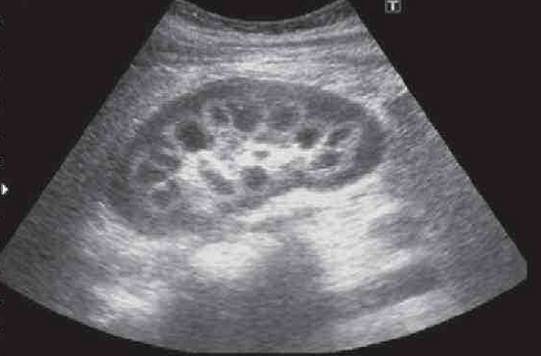

二胎怀到4个月时,经过羊水检测,肚子里的宝宝又患上了和大宝一样的病——肉碱缺乏,在发育过程中不断和妈妈抢夺肉碱。

“我们为了明确孩子的死因,来杭妇院找到了梅主任,她建议我们给宝宝做尸检和基因检查。”王女士说,检查结果发现,孩子有特别严重的心肌病,是原发性肉碱缺乏症引起的,这种病会导致心肌损伤和骨骼肌损伤。